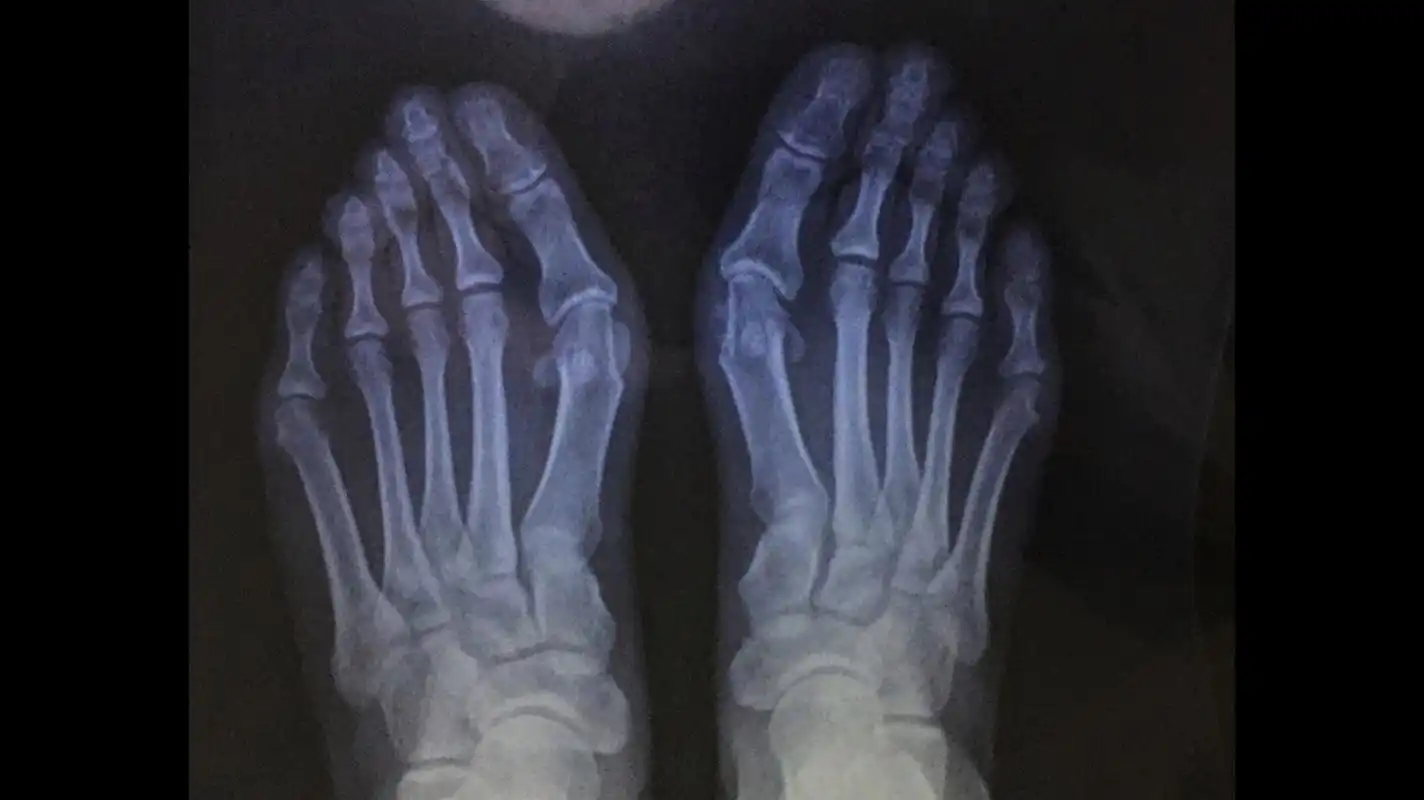

x光片更直观了解大脚骨 如果单纯去掉凸起能否有效矫正拇外翻呢?